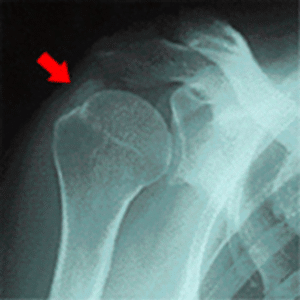

肩 脱臼 【葛飾区金町のやぎはし整体院】肩の脱臼・亜脱臼 「肩が抜けてしまった」という表現をして、病院にいらっしゃる方がいます。 医学的には、「肩関節脱臼」と言われるものです。 肩関節脱臼とは?《金町のやぎはし整体院が解説》 日本整形外科学会HPから掲載 肩関節は、肩甲骨と上腕骨の2つの骨で成り立っています。 何かの原因で、上腕骨が肩甲骨の関節から逸脱し、正常な位置にから外...